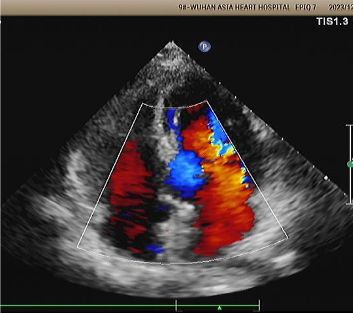

Implan: 2424 MemoSorb®PFO occluber biodegradable disebarkan di bawah panduan gema dan DSA.

Hari 1 sampai 9 bulan:

Tidak ada sisa shunt muncul.

Pengurangan bertahap pada kesopanan perangkat.